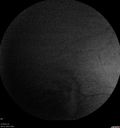

88 year old female with melanosis oculi and 2.5 mm elevated choroidal melanoma. She also has AMD with geographic atrophy. The right eye is the better eye. The left eye had a macular hemorrhage from wet AMD and breakthrough vitreous hemorrhage.